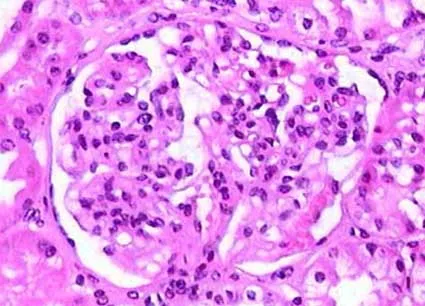

Quando pensar na possibilidade de neoplasias em pacientes com glomerulopatias? Confere esse post com dicas práticas de manejo e rastreio diante da suspeita clínica!

Luís Sette